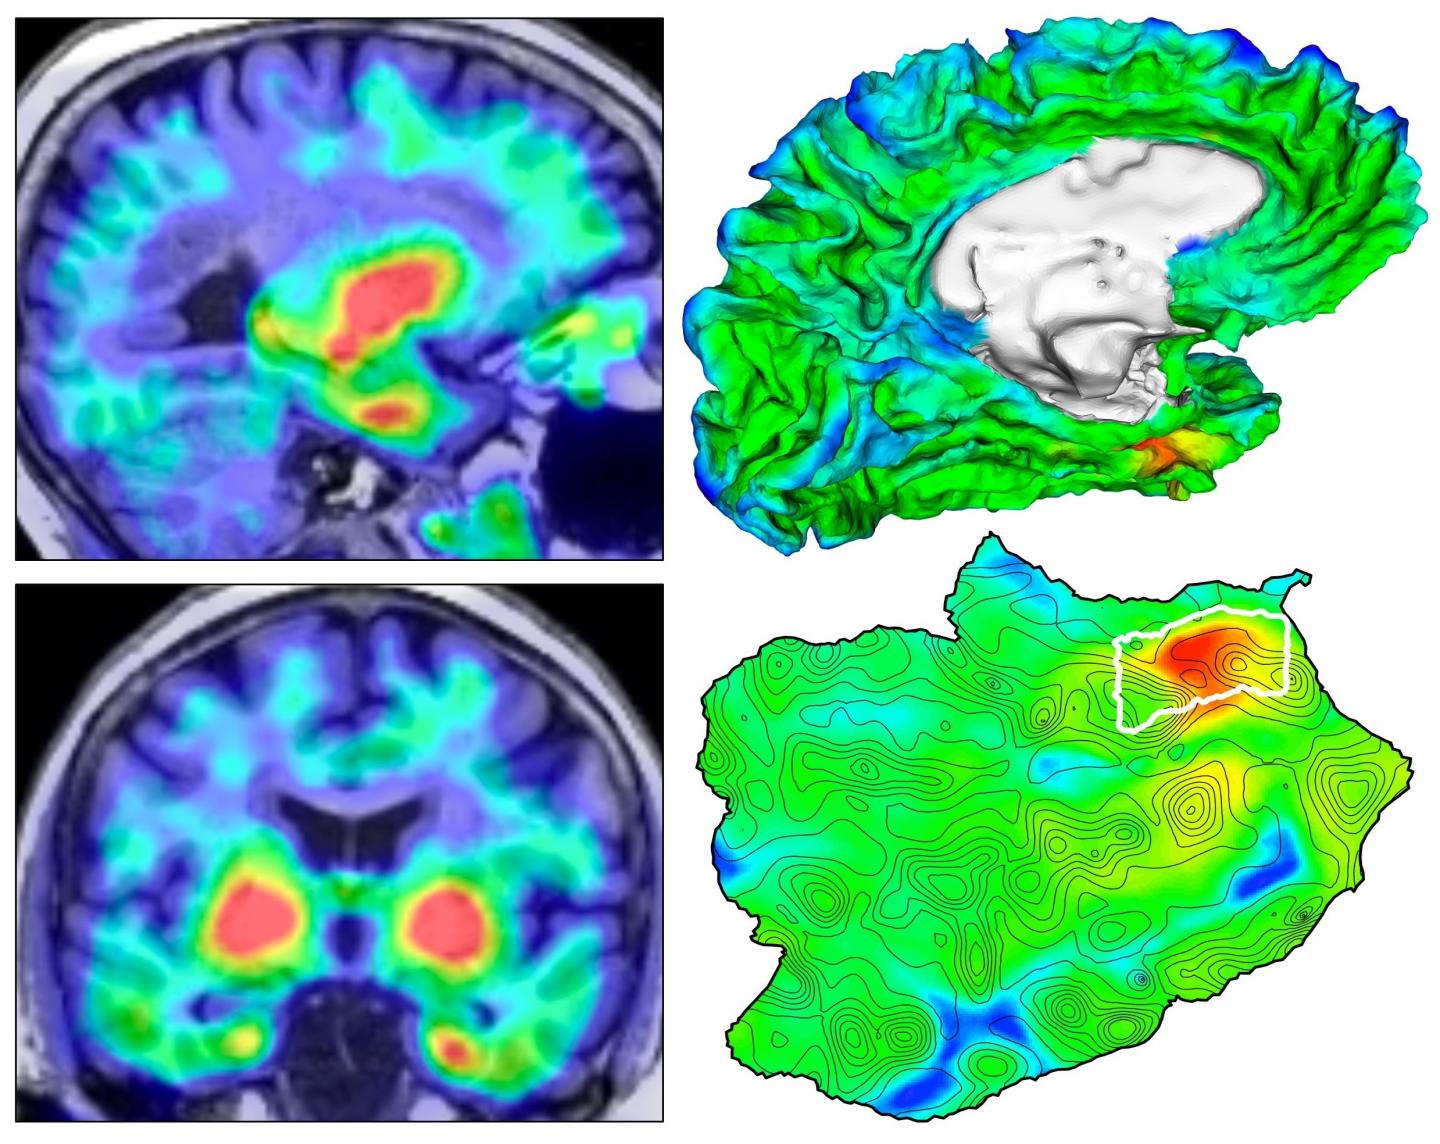

Automated imaging reveals where TAU protein originates in the brain in Alzheimer's disease

image: Four views of the origin of tauopathy in vivo. Left, TAU PET images for a cognitively normal person; right: top, 3D rendering of brain surface with TAU PET overlay; bottom, flat map showing topographic detail of surface anatomy with TAU origin identified in white outline. This material relates to a paper that appeared in the Jan. 20, 2021, issue of Science Translational Medicine, published by AAAS. The paper, by J.S. Sanchez at Massachusetts General Hospital in Boston, MA; and colleagues was titled, "The cortical origin and initial spread of medial temporal tauopathy in Alzheimer's disease assessed with positron emission tomography."

Researchers have developed an automated method that can track the development of harmful clumps of TAU protein related to Alzheimer's disease in the brain, according to work involving 443 individuals. The method revealed that TAU primarily emerged in an area of the brain called the rhinal cortex before spreading elsewhere, suggesting that targeting TAU here could potentially slow the progression of Alzheimer's disease. The buildup of toxic amyloid-beta and TAU proteins is responsible for many of the symptoms and damage to neurons seen in Alzheimer's disease. However, current therapies have shown reduced efficacy, at least in part because the therapies were administered long after the protein had spread throughout the brain. Developing more effective interventions therefore requires a better understanding of where TAU pathology originates and how it spreads. Justin Sanchez and colleagues designed an automated anatomic sampling method that uses PET imaging to track the presence of TAU in the brain. The team applied their technique to 443 adult participants - including 55 patients with Alzheimer's - and discovered that TAU deposits first emerged in the rhinal cortex independently from amyloid-beta before spreading to the temporal neocortex. A two-year experiment with 104 subjects showed that people with the highest initial levels of TAU or amyloid beta displayed the most spread of TAU throughout the brain by the end of the study. "These findings suggest that [the rhinal cortex] is a biomarker of downstream TAU spread ... with potential utility for therapeutic trials in which reduction of TAU spread is an outcome measure," the authors conclude.